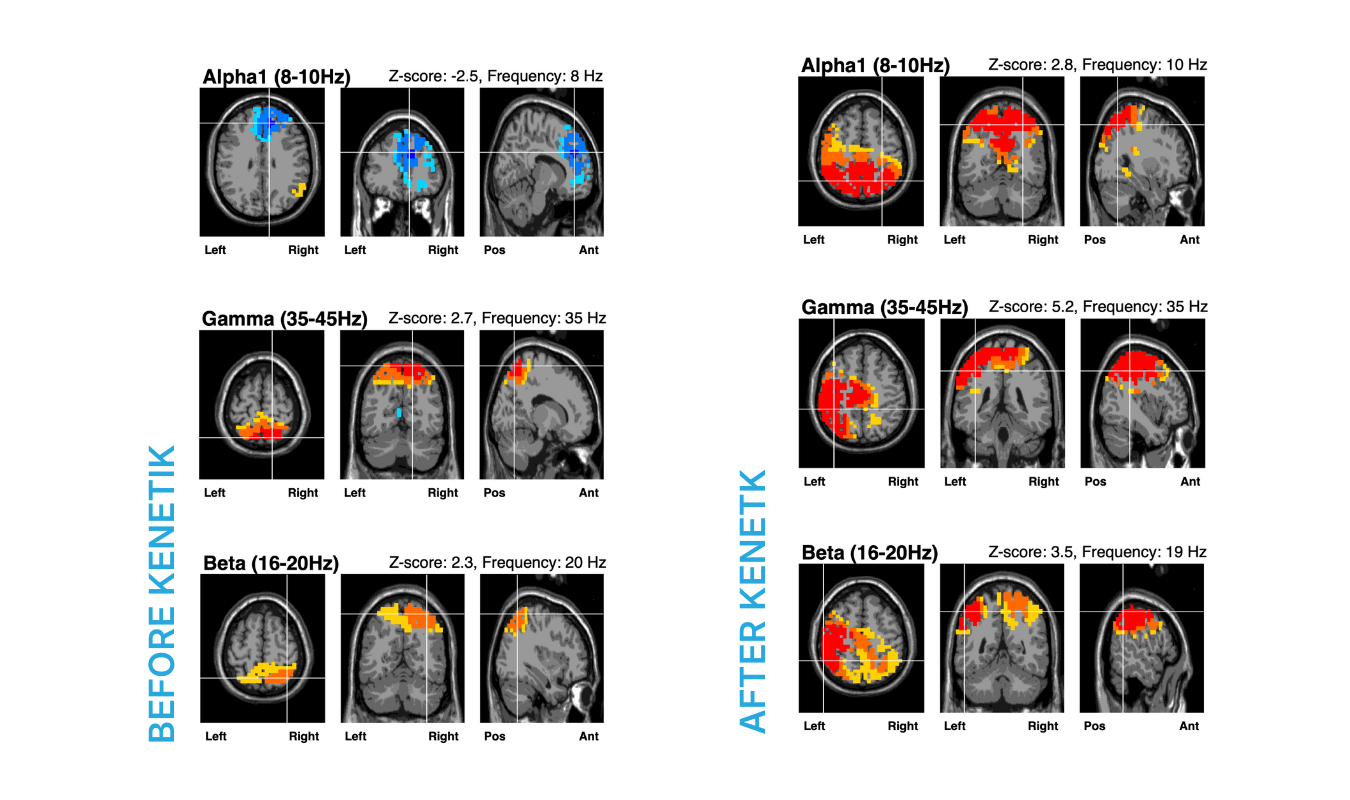

A recent clinical study using qEEG imaging found that one serving of Kenetik directly increases functional brain activity associated with focus and problem solving - also known as your flow state.

+220% Alpha Waves

Alpha waves promote relaxation, creativity, and focus, aiding in stress reduction and concentration on tasks.

+93% Gamma Waves

Gamma waves are crucial for higher mental activities like perception and problem-solving, facilitating memory recall and sensory perception.

+50% Beta Waves

Beta waves promote increased attention, alertness, and awareness - the final piece of the puzzle to get into your flow state.